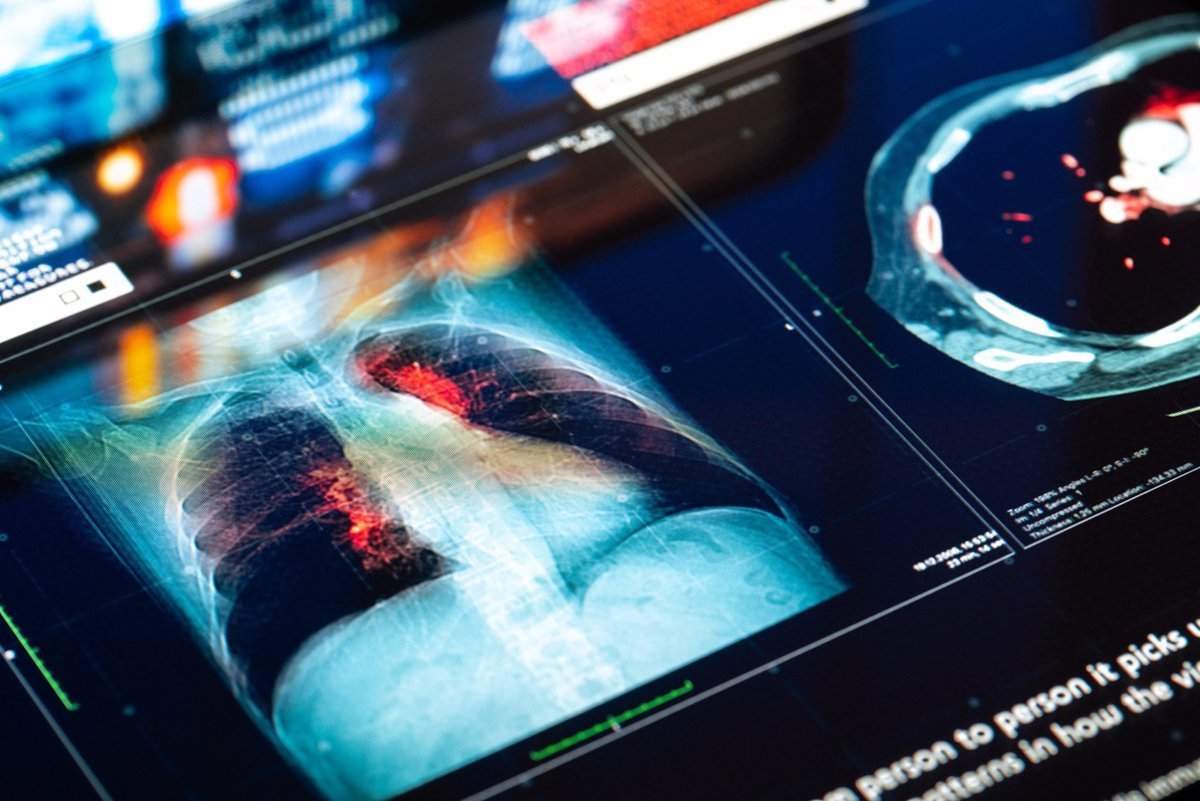

Un grupo de expertos y pacientes ha reclamado este martes en el Congreso de los Diputados la necesidad de implantar el cribado de cáncer de pulmón en España a través de proyectos como CASSANDRA (Cancer Screening Smoking Cessation and Respiratory Assessment), un programa que incorpora la tomografía computarizada (TC) de baja dosis de radiación como herramienta de cribado, en combinación con la deshabituación del tabaco y la colaboración con Atención Primaria.

CASSANDRA se puso en macha en octubre de 2023 y cuenta con la participación de 39 hospitales y centros de atención primaria de 16 comunidades autónomas. El proyecto combina la prevención primaria, mediante la desahabituación tabáquica, y prevención secundaria, con programas de cribado mediante tomografía computarizada (TC) de baja dosis de radiación.